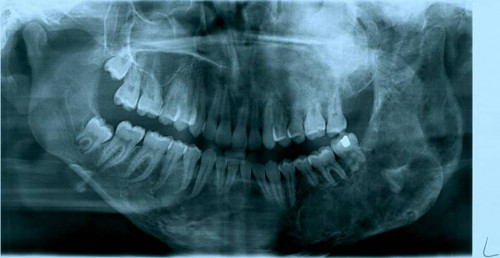

Eine 16-jährige Patientin kommt in eine MKG-chirurgische Praxis zur Abklärung der weiteren Vorgehensweise bzgl. ihrer Erkrankung.

Sie betrachten die angefertigten Röntgenbilder. Welche der folgenden Röntgenbefunde ist korrekt? Ossäre Auftreibungen im Bereich …

- A… der Mandibula links.

- B… des Os frontale links.

- C… des Os zygomaticum links.

- D… des Os temporale links.

- EAlle genannten Aussagen sind korrekt.

Bildgebung - OPAN 2004